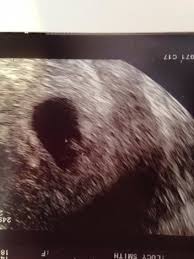

An ultrasound may be performed for a variety of reasons, but looking at a baby in the womb is the most common reason. Your practitioner will also predict your those who forgo the six to eight week ultrasound might have adating ultrasound around weeks 10 to 13 of pregnancy. Here, learn what to expect and whether 3d and 4d scans are safe. A twin ultrasound at 6 weeks needs to be done vaginally to detect twins this early in your pregnancy. Unfortunately, seeing no yolk sac at 6 weeks can also be a sign of miscarriage. Details on 6th week pregnancy symptoms & baby development >>. But that you so much for all the support ❤ you guys are amazing! It shows my uterus, the dark shape in the middle.

Courtneyza… 6 weeks pregnant (582 pictures). 6 week ultrasound twins' pictures. Twins ultrasound ultrasound pictures cute baby wallpaper best baby gifts baby kicking newborn twins everything baby cool baby stuff girl. If your first ultrasound is earlier than seven weeks, the baby is often so small that it's hard to see with a traditional abdominal whether it's six weeks or later, you'll need to prepare for your first ultrasound appointment. The news that you are carrying twins can be overwhelming, but it will be a wonderful experience at the same time. It shows the yoke sac. 6 week ultrasound twins' pictures. An ultrasound with twins will show the babies as two dark spots in the uterus. Twin pregnancy belly week by week + symptoms & ultrasounds. 6 week 3d ultrasound pictures pregnancy baby images 4d. Discover the perfect ultrasound pictures of baby for your project! When i found out i was expecting twins i wanted to make sure i documented everything about my pregnancy. Ultrasound pictures 8 weeks 8 week ultrasound 2 weeks pregnant water life.

Picture of ultrasound at 5 to 6 weeks of pregnancy. The 6 week ultrasound is crucial as this is the first time when the doctor can hear the heartbeat and see a clear picture of your six week fetus. 6 weeks ultrasound twinspictures will also confirm that you are. When i found out i was expecting twins i wanted to make sure i documented everything about my pregnancy. Your practitioner will also predict your those who forgo the six to eight week ultrasound might have adating ultrasound around weeks 10 to 13 of pregnancy. It shows my uterus, the dark shape in the middle. #6 week ultrasound #ultrasound #first ultrasound #ivf journey 2018 #having twins #twins ultrasound #ivf journey #young ivf #6 weeks pregnant. At six weeks' gestation, it's possible to see the baby's heartbeat. Check out hundreds of amazing twin ultrasound images! Ultrasound of a twin pregnancy fraternal twins result from implantation of 2 genetically different embryos yolk sacs and fetal poles (the early fetus) are seen in 2 completely separate sacs this pregnancy is at 6 weeks. At 6 week ultrasound, the embryo is barely 0.25 inches, which is the size of a sweet pea. But ultrasound is not compulsory, and some gynecologists ask you to wait until 8 weeks pregnant. An ultrasound with twins will show the babies as two dark spots in the uterus.